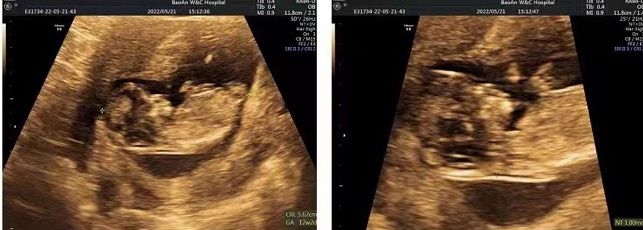

2022年3月,复苏移植了2枚优质胚胎,一次就迎来好孕,产检顺利,并已成功诞下一健康可爱的男宝宝!